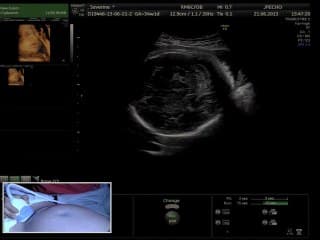

L'auteur décrit l'évolution depuis la cellule germinale primordiale migrant vers le futur ovaire lors de la vie foetale, au follicule mature et l'ovulation chez la femme pubère .Dans cette évolution , 2 phases sont individualisées : -la phase de croissance basale dont la croissance terminale est bloquée par l'AMH. -la FSH va permettre le recrutement cyclique et la phase de croissance terminale qui démarre à la puberté. La réserve ovarienne réelle ( quantité de follicules primordiaux) se situe dans le cortex ovarien ; ces follicules primordiaux mesurent 3 microns , donc sont invisibles à l'échographie . On mesure échographiquement les follicules antraux recrutables dont le diamètre se situe entre 2 à 5mm et dont le nombre est proportionnel à la réserve ovarienne que l'on peut ainsi évaluer. Les petits follicules antraux de 2 à 5 mm ont une sensibilité variable pour la FSH et ainsi le 1er follicule ayant atteint le seuil de FSH sera sélectionné comme dominant et va évoluer vers l'ovulation, et par la production d'oestradiol par ce follicule dominant associée à la chute de la FSH ,les autres follicules antraux vont devenir atrétiques. En pratique , c'est le nombre de follicules de 2 à 5mm ( recrutables) , visibles à l'échographie qui est le reflet de la réserve ovarienne et qui est le facteur prédictif de la réponse à la stimulation ovarienne ; mais ce n'est pas un facteur prédictif de grossesse. Pour le déclenchement de l'ovulation lors d'une stimulation ovarienne, on estime que le follicule est mature lorsqu'il atteint 17-18mm ; toutefois des follicules de 14-15mm peuvent aussi être fécondables . Un follicule supérieur à 10mm à J3 ou supérieur à 15mm à J8 correspond à un recrutement précoce et serait le signe d'une insuffisance ovarienne .

L'auteure rappelle à travers des cas cliniques et son expérience les informations indispensables que l'échographie apporte lors d'une prise en charge en PMA. Elle en profite pour présenter une revue claire et concise des types de stimulation ovarienne, qui pourra s'avérer utile aux praticiens ne manipulant pas ces protocoles au quotidien.

Nicolas Perrot différencie la pathologie fonctionnelle de la pathologie organique lors du 1 er bilan échographique en AMP , qui sera réalisé par voie endovaginale.PATHOLOGIE FONCTIONNELLE:Kyste fonctionnel liquidien pur: > 3 cm ,qui peut être documenté plus précisément en 3D.Son caractère fonctionnel sera affirmé par sa disparition spontanée lors d'un contrôle à 2 mois.Le diagnostic différentiel d'un kyste uniloculaire sera le cystadénome séreux ou mucineux , qui persistent.Autre diagnostic différentiel: l'hydrosalpinx ancien dans sa portion ampullaire( disparition des franges), parfois labile.Le kyste paratubaire qui peut présenter un petit nodule fibreux intrakystique.Kyste à contenu solide: intérêt du Doppler.le kyste lutéal( évolutif et transitoire): cloisons de fibrines , caillots , contenu avasculaire , paroi hypervascularisée.le kyste multiloculaire liquidien.PATHOLOGIE ORGANIQUE:Endométriome, qui peut poser un problème de diagnostic différentiel avec le kyste lutéal en cas de saignement intrakystique récent. Les dépôts cruoriques sont pathognomoniques. Necessite d'évaluer la réserve folliculaire adjacente et de rechercher des signes d'endométriose profonde.Dermoïde"White Ball" avasculaire , hétérogène( sébum et plages hyperéchogènes).L'IRM "fat sat" différencie dermoïde et endométriome.Kyste avec végétations vasculaires( carcinome , border line).Plus rares:Pseudokyste péritonéal, triangulaire, de grande taille, moulant la paroi pelvienne.GEU séquellaire fibreuse avec tissu trophoblastique avasculaire.Kyste de Tarlov, petit , postérieur( issu d'un trou de conjugaison) . Diagnostic IRM.